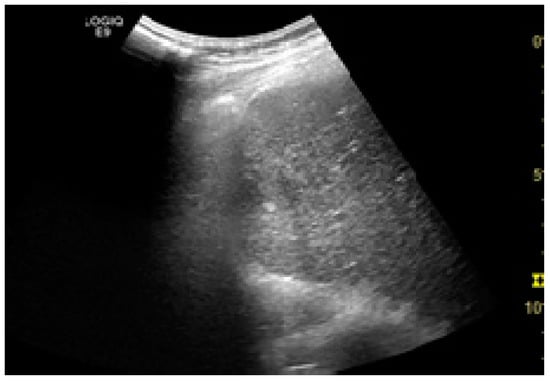

Among the factors associated with US detection performance, tumor size is one of the most important predictors, as larger nodules consistently lead to higher sensitivities. In one recent study, the sensitivity of US was 90%, 84%, 76%, and 65% for nodules larger than 4 cm, 3–4 cm, 2–3 cm, and 1–2 cm, respectively []. Infiltrative tumors are much more difficult to detect via US and are more often associated with surveillance failure [,]. In one study on 304 HCC patients who received regular surveillance with US and AFP, the failure rate was significantly higher for patients with infiltrative type tumors (57.1%) compared to nodular tumors (2.1%) []. Regarding echogenicity, isoechoic and faint hypo/hyperechoic lesions may escape a regular US evaluation (Figure 1 and Figure 2) [,]. The US visualization of nodules located in a deep or subcapsular position and/or near lung tissue (segments VII, VIII, and IVa) might be very difficult, or sometimes even impossible [,].

Figure 1.

Small hypoechoic hepatocellular carcinoma (HCC) in a cirrhotic liver. US evaluation.